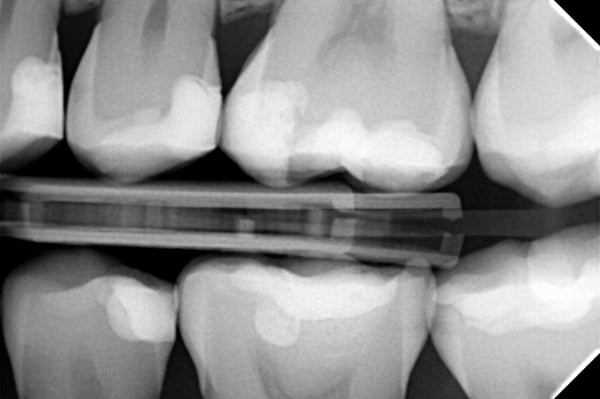

After the polishing process, the filling was coated with a surface liner (PermaSeal™ composite sealer, Ultradent Products). Occlusal and radiography control followed.

As it can be seen by the final pictures, Transcend composite offers an exceptionally esthetic appearance for the restoration. The Halo sectional matrix system allowed for a great proximal anatomy, as it can be seen on the radiograph.